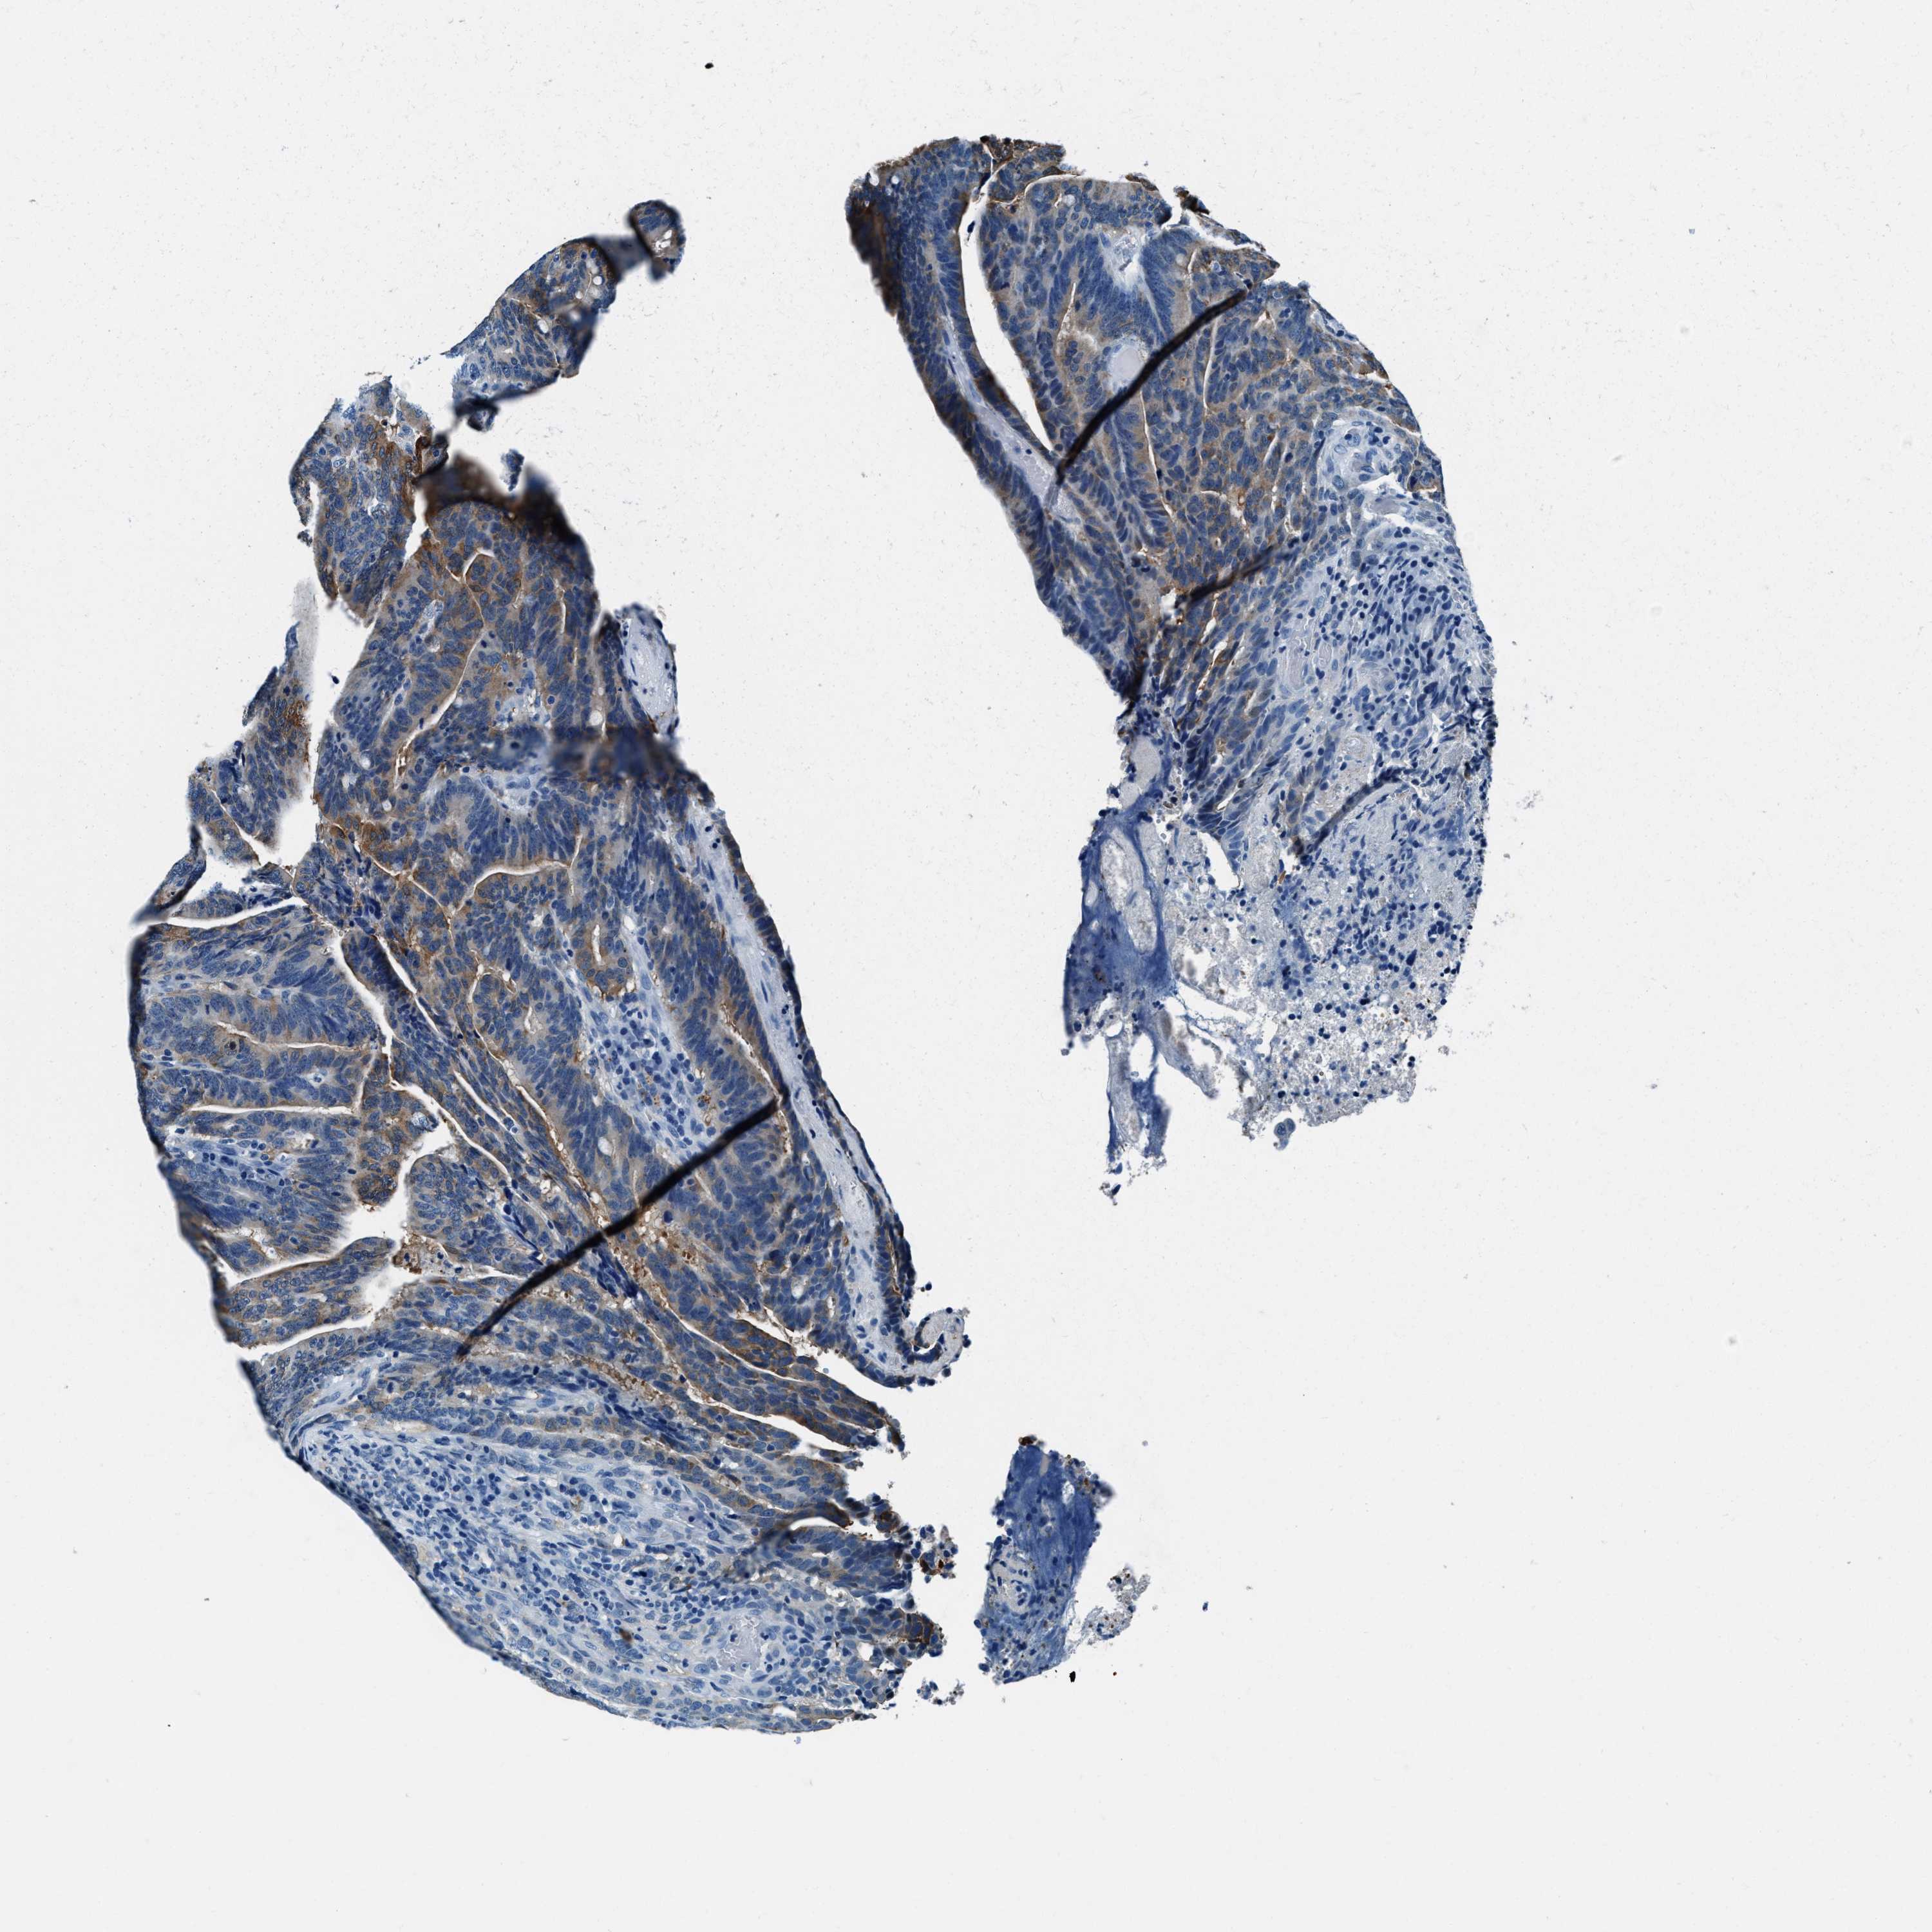

CANCER COLORECTAL CANCER Show tissue menu

Colorectal cancer

Rectum adenocarcinoma